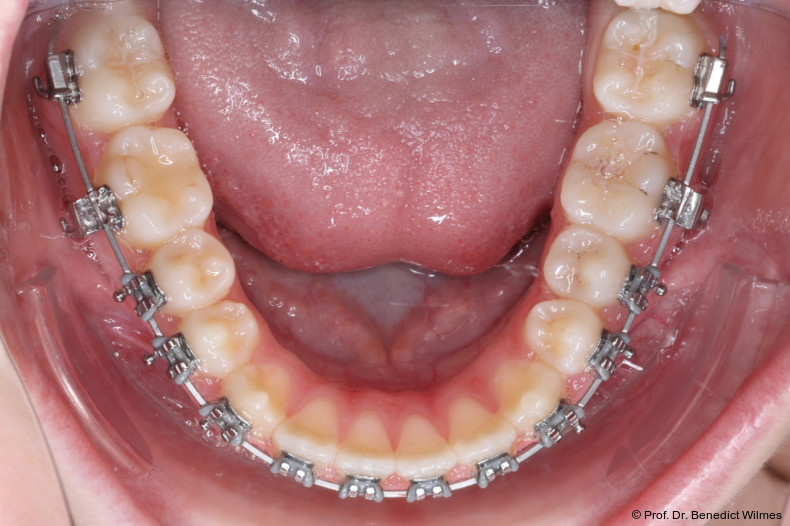

Nach erfolgreicher Expansion und Molaren­intrusion wurde eine Multibracket-Therapie zur Ausformung und Koordination der Zahnbögen durchgeführt (Abb. 8a–f). Nach Abschluss der aktiven Behandlungsphase wurden die Apparaturen entfernt und festsitzende Retainer im Ober- und Unterkiefer eingesetzt (Abb. 9a–k).